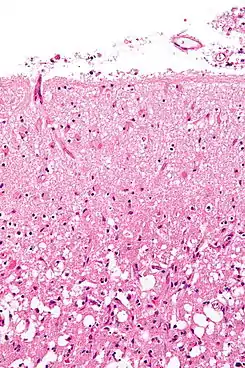

La astrogliosis (también conocida como astrocitosis o astrocitosis reactiva) es un aumento anormal en el número de astrocitos debido a la destrucción de las neuronas próximas por un trauma en sistema nervioso central (SNC), infección, isquémia cerebral, un accidente cerebrovascular, una respuesta autoinmune y una enfermedad neurodegenerativa. En el tejido neuronal saludable, los astrocitos desempeñan un papel crítico al proporcionar energía a las neuronas, regular el flujo sanguíneo, la homeostasis del fluido extracelular así como de los iones y transmisores, y regular la función sináptica y el remodelado sináptico.[1][2] La astrogliosis cambia la expresión molecular y la morfología de los astrocitos, provocando la formación de cicatrices y, en casos graves, la inhibición de la regeneración de axones.[3][4]

![]() Formación de astrocitos reactivos después de una lesión al sistema nervioso central | ||